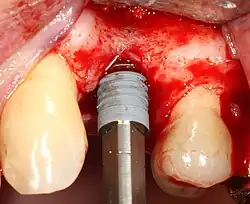

Most implant systems have five basic steps for placement of each implant:[28]: 214–221

- Drilling at high speed: After reflecting the soft tissue, and using a surgical guide or stent as necessary, pilot holes are placed with precision drills at highly regulated speed to prevent burning or pressure necrosis of the bone.

- Drilling at low speed: The pilot hole is expanded by using progressively wider drills (typically between three and seven successive drilling steps, depending on implant width and length). Care is taken not to damage the osteoblast or bone cells by overheating. A cooling saline or water spray keeps the temperature low.

- Placement of the implant: The implant screw is placed and can be self-tapping;[50]: 100–102 otherwise, the prepared site is tapped with an implant analog. It is then screwed into place with a torque controlled wrench[54] at a precise torque so as not to overload the surrounding bone (overloaded bone can die, a condition called osteonecrosis, which may lead to failure of the implant to fully integrate or bond with the jawbone).